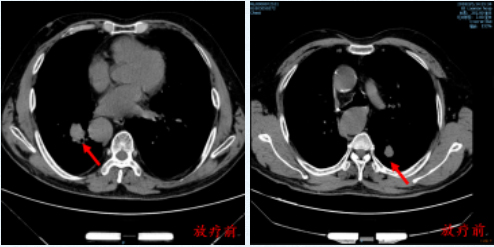

图为 放疗前胸部CT显示病灶位置

2018年3月,经我院肿瘤放疗科会诊后分别给予双肺转移灶立体定向放疗,放疗方案为:

右肺转移灶:PTV/60Gy/8f,左肺转移灶:PTV/60Gy/8f,共 3周完成治疗,过程顺利,未见明显毒副反应。